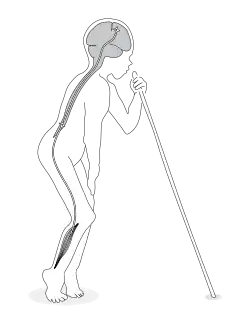

| A boy affected by konzo displaying the typical gait. The upper motor neuron is the suspected neurodamage site. | |

The onset of paralysis (spastic paraparesis) is sudden and symmetrical, and affects the legs more than the arms. The resulting disability is permanent but does not progress. Typically, a patient is standing and walking on the balls of the feet with rigid legs and often with ankle clonus.[7]

The severity of konzo varies; cases range from only hyperreflexia in the lower limbs to a severely disabled patient with spastic paraparesis, associated weakness of the trunk and arms, impaired eye movements, speech and possibly visual impairment. Although the severity varies from patient to patient, the longest upper motor neurons are invariably more affected than the shorter ones. Thus, a konzo patient with speech impairment always shows severe symptoms in the legs and arms.

Depending on its severity, konzo is divided into three categories: mild when individuals are able to walk without support, moderate when individuals need one or two sticks to walk, and severe when the affected person is unable to walk unsupported.[12]

"Konzo" means "tied legs" in the Yaka language of southwestern DR Congo and was the designation by the first affected population in DR Congo as reported by Dr G. Trolli in 1938. The name, taken up by Hans Rosling[32] and colleagues, aptly describes the typical spastic gait of those affected.